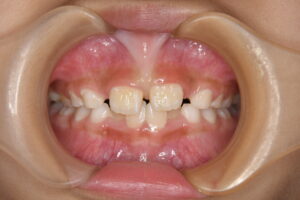

上唇をめくったときに 上の前歯のちょうど真ん中にあるすじのことです。

この状態のことを 〖上唇小帯高位付着〗といわれます。

上の前歯が生え変わる小学校低学年のころに小帯が長いままでいると、前歯の間に隙間ができる原因になることがあります。これを〖正中離開〗と呼び、前歯が通常よりも離れて生えてしまう、いわゆる『すきっぱ』になるという現象です。前歯の隙間は、前歯の隣の歯や後ろの歯の生える力によって隙間が狭くなることもありますが、長いままであると完全に隙間が閉じるということはなかなか難しくなります。